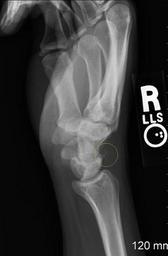

MAKE A MEME View Large Image AvulsionfractureXRay.jpg This is an x-ray of my injured wrist I injured it by falling while on a road bike I landed in a seated position bracing my fall with my right hand/wrist The diagnosis was Avulsion fracture off lunate bone It's a ...

Keywords: AvulsionfractureXRay.jpg This is an x-ray of my injured wrist I injured it by falling while on a road bike I landed in a seated position bracing my fall with my right hand/wrist The diagnosis was Avulsion fracture off lunate bone It's a small fracture so it's difficult to see en wikipedia Sreejithk2000 CommonsHelper 2007-09-05 Vanalstm wikipedia en Vanalstm original upload log page en wikipedia AvulsionfractureXRay jpg 2007-09-05 15 58 Vanalstm 1054×1611× 105245 bytes <nowiki>This is an x-ray of my injured wrist I injured it by falling while on a road bike I landed in a seated position bracing my fall with my right hand/wrist The diagnosis was Avulsion fracture off lunate bone It's a small fracture so it's difficult to</nowiki> 2007-09-05 15 55 Vanalstm 1054×1611× 103545 bytes <nowiki>This is an x-ray of my injured wrist I injured it by falling while on a road bike I landed in a seated position bracing my fall with my right hand/wrist The diagnosis was Avulsion fracture off lunate bone It's a small fracture so it's difficult</nowiki> X-rays of hand fractures Medical treatments Fractures of human triquetrum